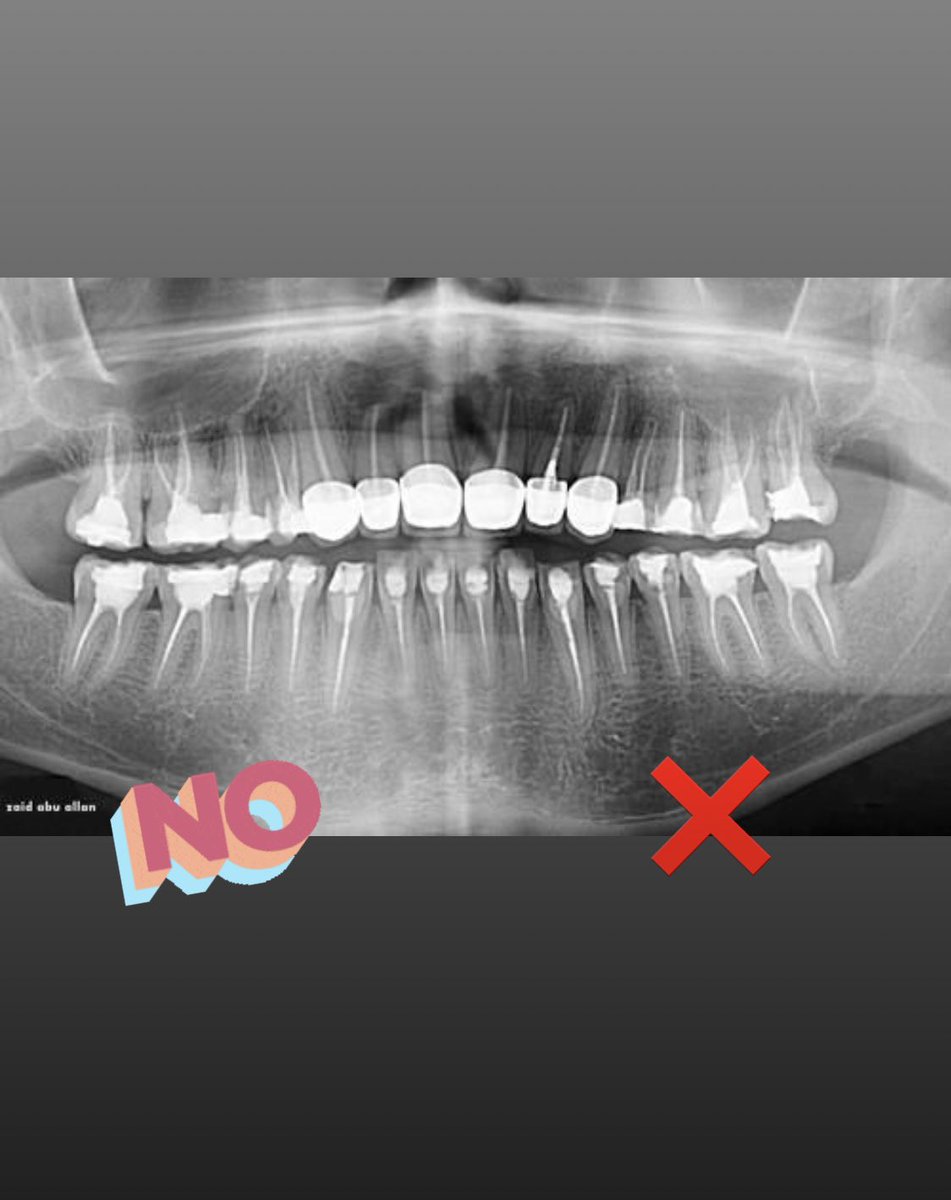

اذا تم تثبيت العدسات فوق الاسنان بدون برد سيؤدي الى بروز الاسنان والتهاب اللثه وتجمع الاكل

في حالات معينه جدا يمكن عملها بدون برد عندما تكون الاسنان اصغر من حجمها الطبيعي او عند وجود فراغات